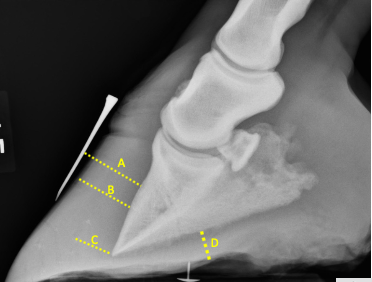

Je pense que le cheval a de la fourbure et pour le confirmer, je désire mesurer la distance entre la muraille et P3. Quelle ligne représente le mieux la distance désirée?

A, B, C ou D

A